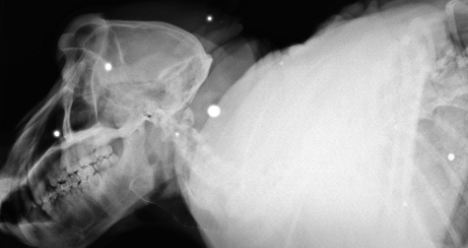

Τον τρόμο είχε σπείρει σε μία πόλη της Νότιας Αφρικής, ένας μπαμπουίνος ο οποίος συνήθιζε να επιτίθεται σε ανθρώπους και να κλέβει τρόφιμα! Μάλιστα, μέχρι να αιχμαλωτιστεί από τις Αρχές της πόλης είχε φανεί... πολύ σκληρός για να πεθάνει, μιας και είχε δεχθεί πάνω από 50 σφαίρες!Οι σφαίρες φάνηκαν μετά από ακτινογραφίες τις οποίες πραγματοποίησαν στον μπαμπουίνο κτηνίατροι, μετά την θανάτωση του από τις Αρχές του Κέιπ Τάουν.

Ο Fred, όπως είναι η ονομασία που οι κάτοικοι είχαν δώσει στο ζώο, είχε μάθει να ανοίγει τσάντες και να κλέβει φαγητό από αυτοκίνητα και σπίτια παρά τους πυροβολισμούς που είχε δεχτεί στο σώμα και το κεφάλι. Αρκετοί άνθρωποι, μέχρι τη στιγμή που αιχμαλωτίστηκε, είχαν νιώσει τα δόντια του Fred, ο οποίος προκειμένου να αμυνθεί δάγκωνε.